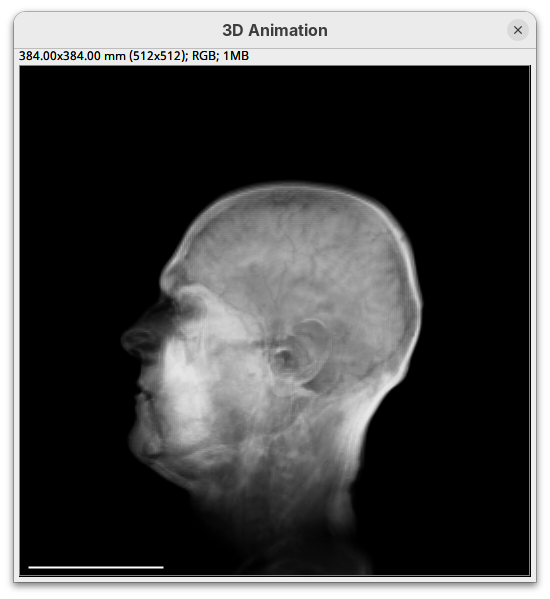

Two new windows will open: 3D Animation with the initial rendering of the data and Interactive Raycaster with all the fields to control the rendering parameters.

Contrast

By default 3Dscript sets the gamma value of alpha to 2.0. That’s a good default for fluorescence microscopy (see the next dataset below), but since this is MRI data, we need to tweak it a little differently.

- Set the alpha gamma value to

1.0.

Note that this improves the visualization as the head’s surface becomes better visible.

- To compare, set alpha

maxto5000.

You will notice that the sample will become more transparent. Even the brain inside the skull will be visible.